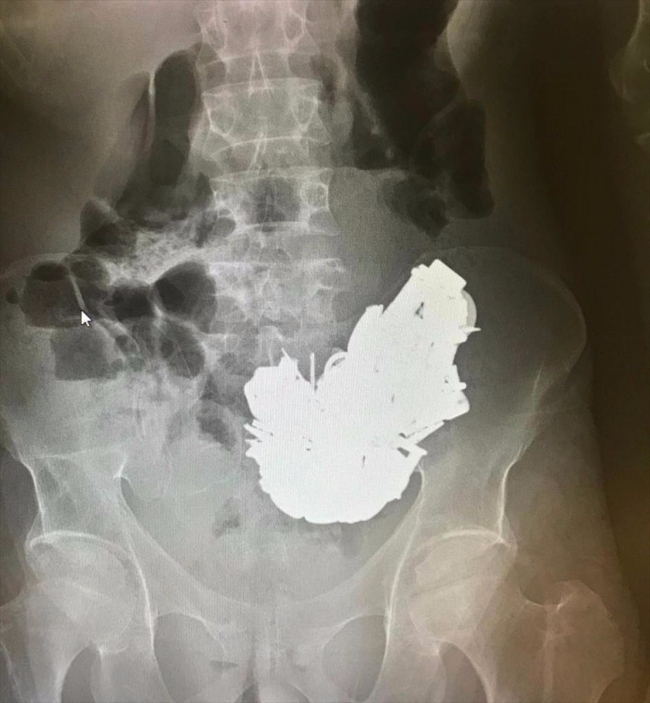

Doktorlar, röntgen filminde midede çok sayıda cisim bulunduğunu tespit etti. Sağlık durumu kötüleşen hasta için acil ameliyat kararı verildi.

Hastanın midesindeki farklı boyutlarda ve toplam 580 gram ağırlığında yaklaşık 200 cisim, 3 saat süren ameliyatla alındı.

Hastanın midesinden çıkarılan cisimler arasında bulunan mıknatıs, anahtar, boş kovan, çivi, cıvata, anahtarlık, madeni para, metal harfler ve çeşitli boyuttaki metaller, sağlık personelini şaşırttı.

Midedeki metallerin mıknatıs sayesinde bir arada toplanması, röntgen görüntüsüne de yansıdı.